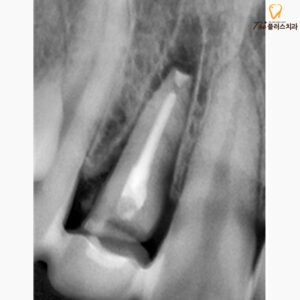

치아 재식술을 통해 신경치료가 이루어졌으며,

본래의 위치에 다시 제 식립한 모습입니다.

또한 원래 위치에 이식한 치아의 경우

자리를 잡는 데에 시간이 필요합니다.

또한,

환자분의 경우 상태가 좋지 못해

예후가 좋지 않을 수 있어

상태를 지속적으로 체크해야 합니다.

정기적인 검진을 통해

환자분의 치아 뿌리의 안정성을

지속적으로 경과를 관찰하였습니다.